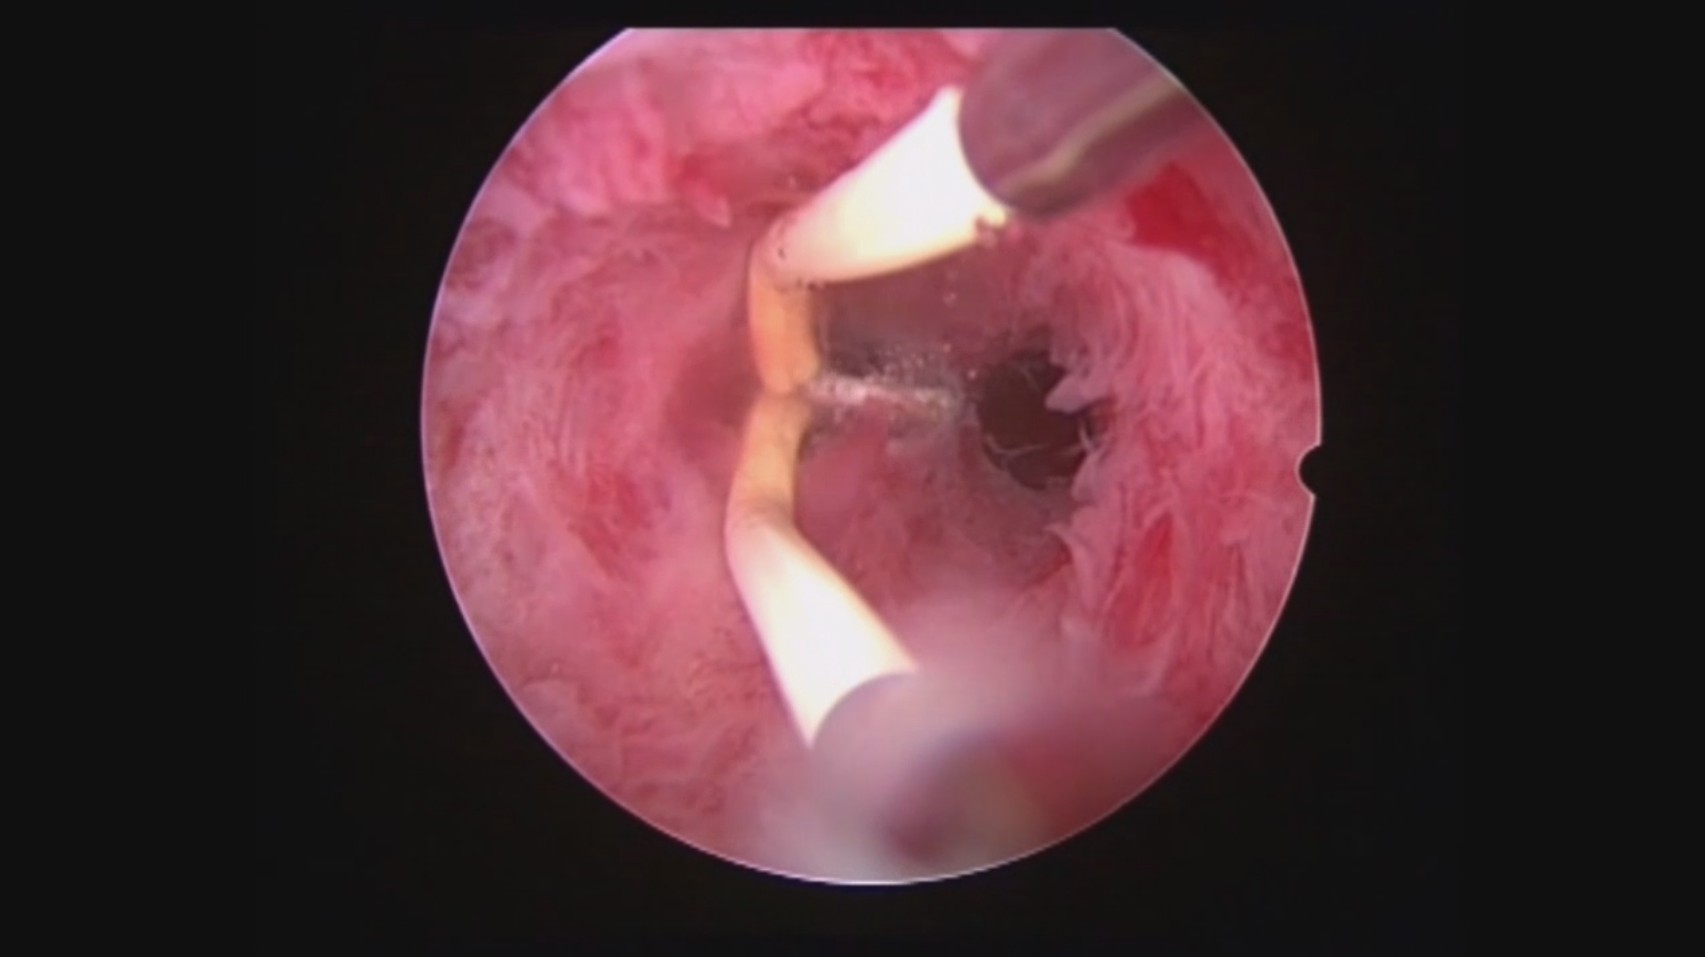

患者32岁,G6P0,继发不孕,2017年8月行宫腔镜探查,发现宫腔两侧及宫底致密粘连,尤其是宫腔右侧多重粘连,宫腔狭小。单极电切分粘,恢复宫腔形态,显露双侧输卵管开口。2018年8月自然妊娠40多天,我在兰州大学附一院生殖中心进修,病人微信发B超给我,大孕囊,胎心微弱,外院疑诊胚胎停育,拟行清宫,嘱病人不要轻易清宫,继续保胎1周,复查B超,胚胎发育正常。病人的信心和坚持成就了她自己和孩子的奇迹,孕期顺利,足月分娩。后病人再次妊娠1次,人流终止妊娠,现41岁,G8P1。